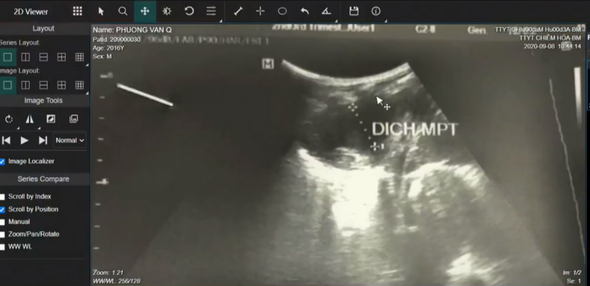

Hình ảnh siêu âm khu vực phổi của bệnh nhân 4 tuổi ở Chiêm Hóa.

TTYT huyện Chiêm Hóa cho biết, bệnh nhân P.V.Q (4 tuổi, trú tại xã Trung Hòa, huyện Chiêm Hóa) nhập viện ngày 7/9/2020, do đau ngực trái. Bệnh nhân được chẩn đoán tràn dịch màng phổi, viêm phổi.

Cũng theo TTYT huyện Chiêm Hóa, cách ngày vào viện khoảng 20 ngày, bệnh nhân xuất hiện đau tức ngực trái, đau âm ỉ liên tục, đau tăng lên khi vận động kèm theo khó thở nhẹ, sốt nhẹ 3 ngày theo từng cơn với nhiệt độ là 38 độ C, sút cân nhanh… Bệnh nhân có sử dụng thực phẩm chưa thực sự chín trước đó.

Với các triệu chứng lâm sàn trên, TS Nguyễn Thành Nam – Trưởng khoa Nhi (Bệnh viện Bạch Mai) đã đề nghị TTYT huyện Chiêm Hóa thực hiện thêm các xét nghiệm loại trừ lao màng phổi.

Tuy nhiên, do lo ngại tập quán sinh hoạt tại địa phương và trước đó, bệnh nhân đã sử dụng cua đá nên PGS.TS Đỗ Duy Cường – Giám đốc Trung tâm Bệnh nhiệt đới (Bệnh viện Bạch Mai) đề nghị sàng lọc thêm các bệnh khác như ký sinh trùng, vi khuẩn.

PGS.TS Đỗ Duy Cường cho biết: “Về dịch tễ học nói chung ở vùng miền núi phía Bắc thì không chỉ riêng các cháu nhỏ, kể cả người lớn đều có thói quen hay ăn cua nướng, hoặc các đồ thực phẩm chưa thực sự chín nên không loại trừ trường hợp bị sán lá phổi xâm nhập rồi gây nên tình trạng xuất hiện nhiều dịch mủ trong khu vực phổi. Vì vậy, tôi đề nghị TTYT huyện Chiêm Hóa thực hiện thêm các xét nghiệm, soi chiếu về ký sinh trùng, vi khuẩn… ở khu vực phổi”.

Đồng quan điểm với các ý kiến trên, PGS.TS Phan Thu Phương – Giám đốc Trung tâm Hô hấp (Bệnh viện Bạch Mai), cùng các chuyên gia khác tại buổi hội chẩn đề nghị TTYT huyện Chiêm Hóa dẫn lưu dịch màng phổi, thực hiện xét nghiệm soi trực tiếp về ký sinh trùng, vi khuẩn, nấm.